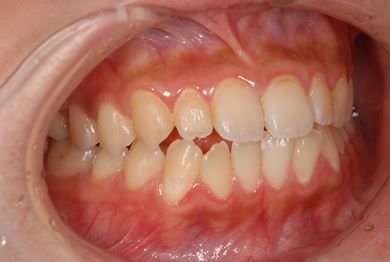

治療前

• 治療前